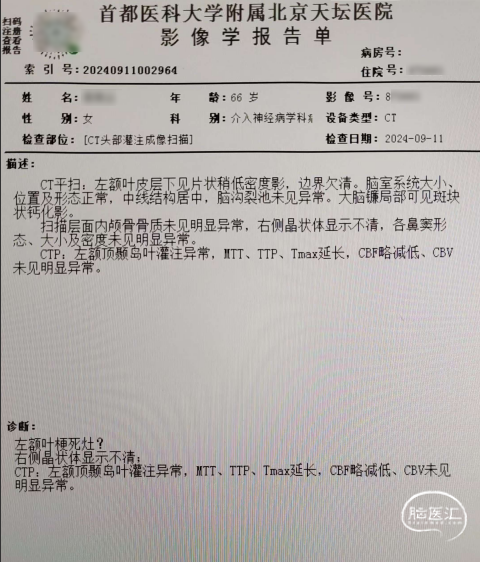

入院头CTP结果影像及报告(2024-09-11)。